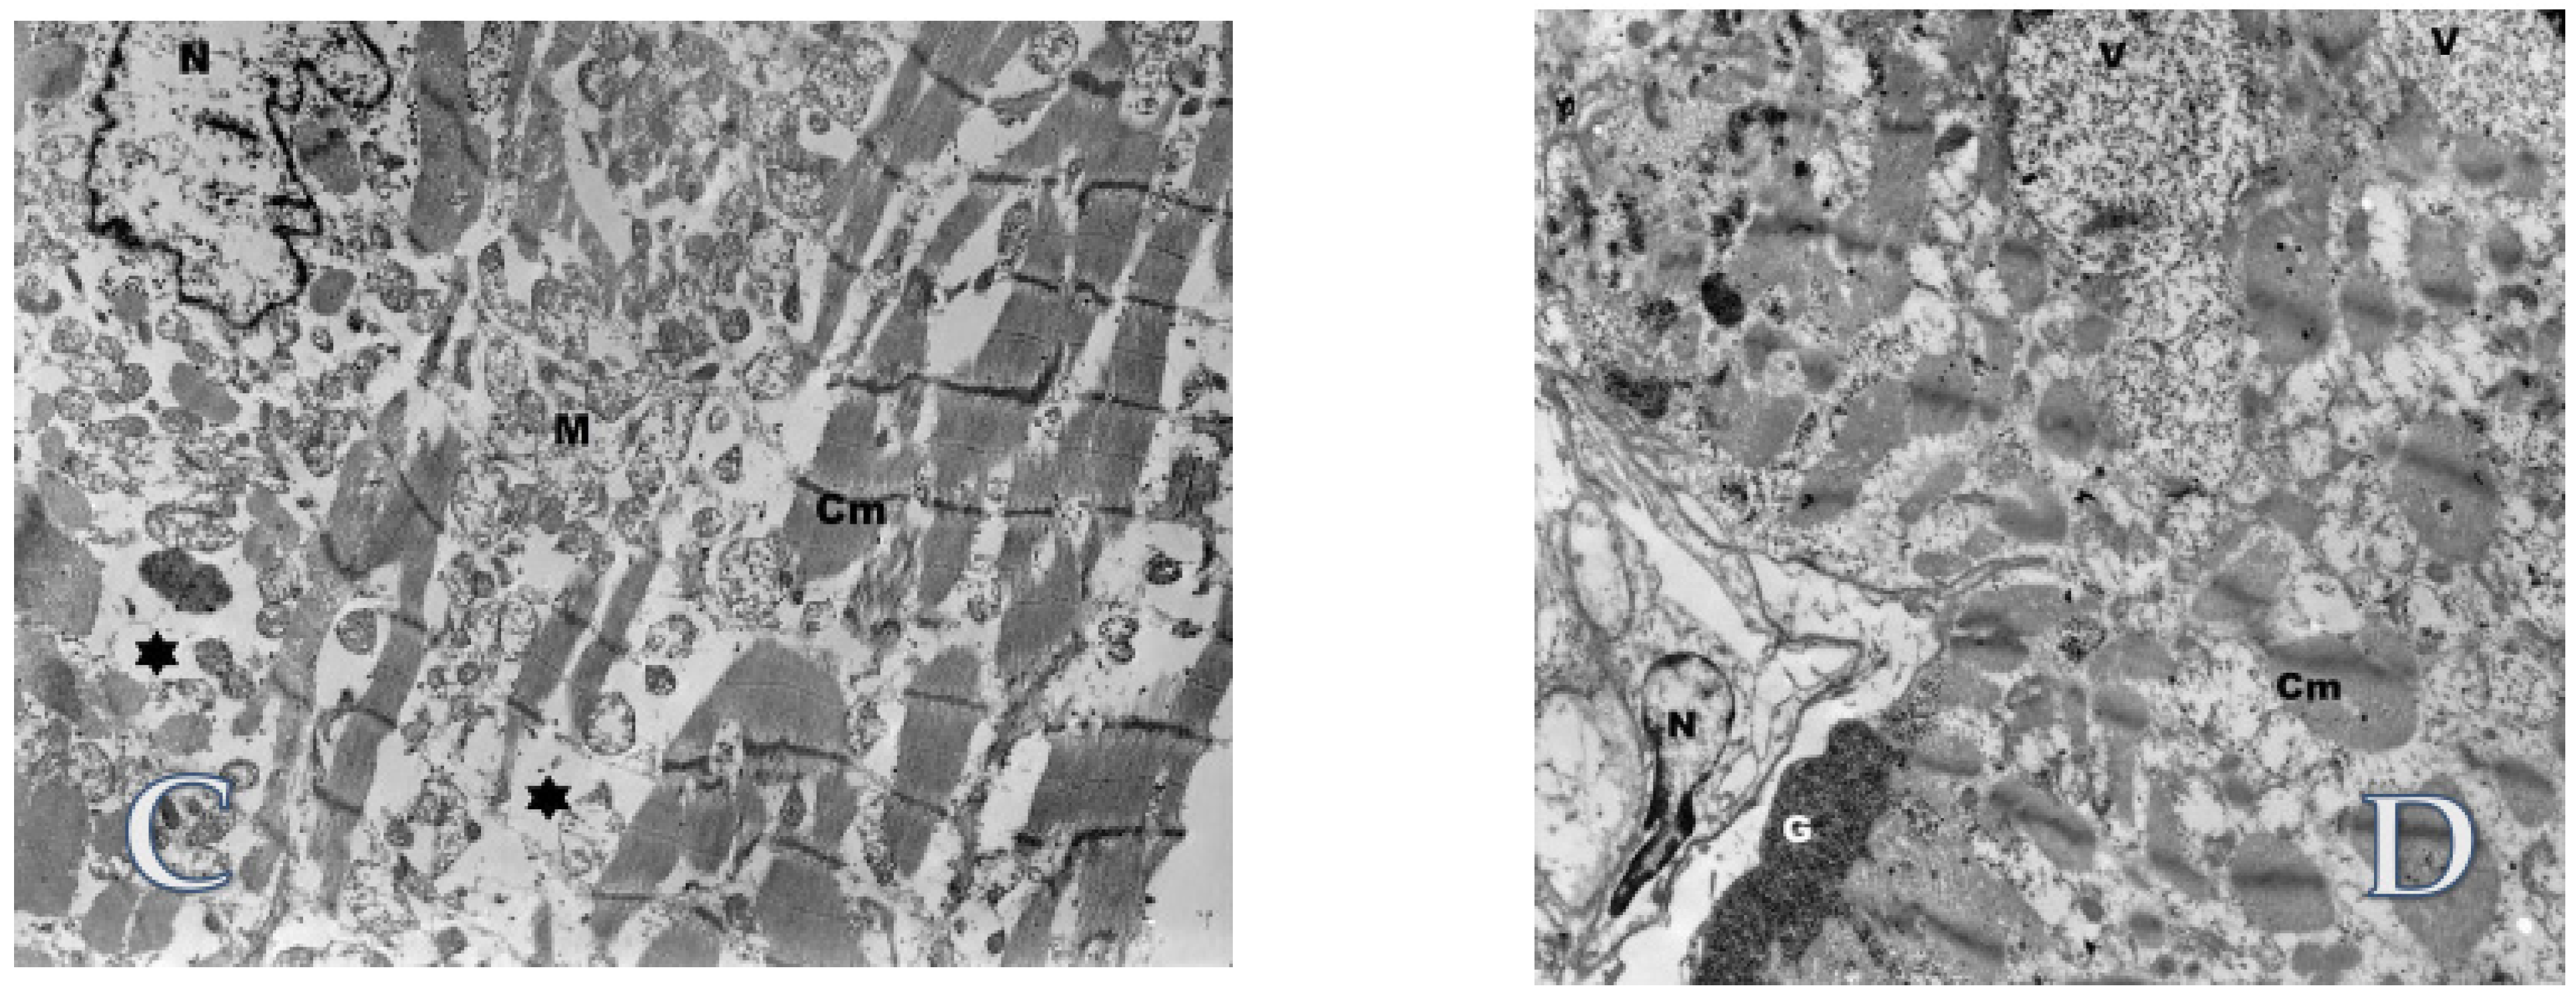

Subsequent ultra-structural analysis (Figure 8) of cardiomyocytes showed enlarged and bizarre shaped nuclei, extensive loss of myofibrils with formation of vacuoles, numerous swollen mitochondria, and accumulation of glycogen in sarcoplasm. There was no accumulation of lipofuscin as well as ultrastructural profiles of curvilinear or fingerprint bodies and granular osmiophilic deposits (GRODs) in lysosomes, characteristic of NCLs.

Figure 8.

Transmission electron microscopy studies of the biopsy specimens obtained from explanted heart. (A) Cardiomyocyte (Cm) in longitudinal section. Numerous swollen mitochondria (M) and glycogen (G) in the sarcoplasm are visible. Original magnification: ×7000; (B) Cardiomyocyte (Cm) in cross section. Accumulation of glycogen (G) in an area with loss of myofibrils. Original magnification: ×3000; (C) A bizarrely shaped cell nucleus (N) in the sarcoplasm of the cardiomyocyte (CM). Multiple loss of myofilaments (asterisk) and accumulation of damaged mitochondria (M). Original magnification: ×4400; (D) Extensive loss of myofibrils in cardiomyocyte (Cm). The vacuoles (V) with dispersed glycogen are visible and also the accumulation of glycogen (G) near the sarcolemma. Nucleus (N). Original magnification: ×4400.

Ultra-structure analysis of the explanted heart from our patient revealed enlarged and bizarre shaped nuclei, extensive loss of myofibrils with formation of vacuoles, numerous swollen mitochondria, and accumulation of glycogen in sarcoplasm of cardiomyocytes. Danon disease, as well as other glycogenosis, have been ruled out after whole exome sequencing. Interestingly, this picture resembles findings described in heart tissue samples from patients with dilated cardiomyopathy of unknown origin, in which changes observed in electron microscopy consisted also of enlargement and varying shape of nuclei, numerous very small mitochondria, proliferation of T tubules, and accumulation of lipid droplets and glycogen. Lipofuscin, myelin figures, and vacuoles were numerous. The most prominent alteration was the loss of contractile elements resulting in large cellular areas filled with non-specified cytoplasm containing only mitochondria, ribosomes, and glycogen [36].